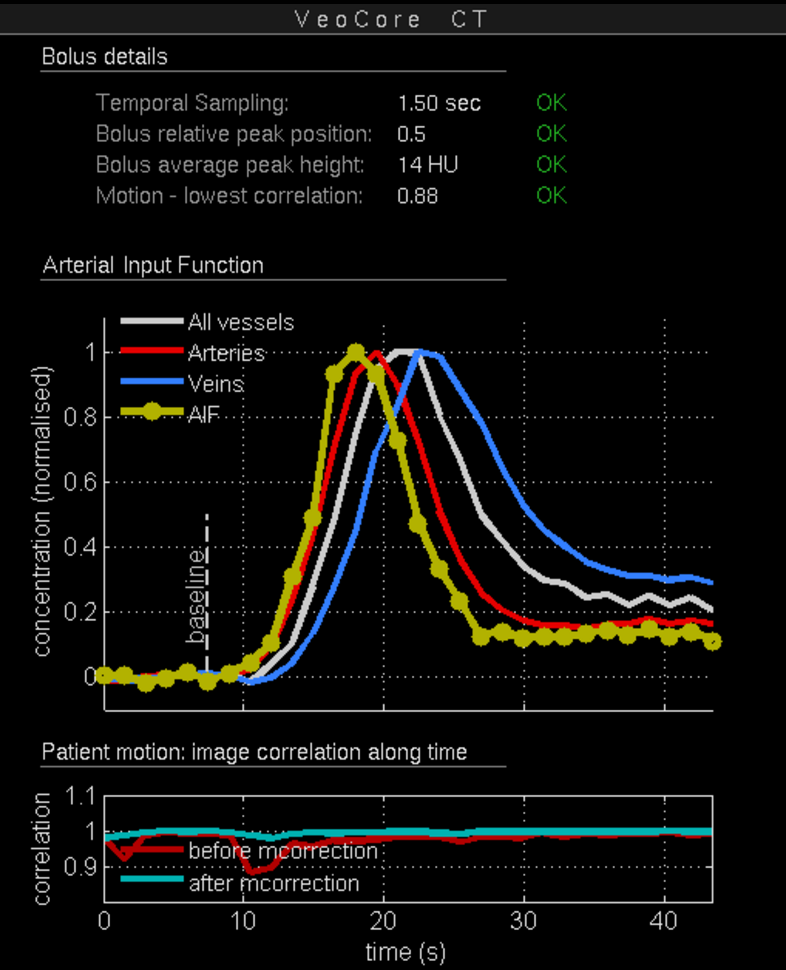

Des Weiteren ist mRay in der Lage eine Verarbeitung von Bildern durchzuführen und so Veränderungen bzw. Anomalien in Geweben zu finden, zu visualisieren und zu quantifizieren. Das Bildverarbeitungsmodul mRay VEOcore kann verwendet werden, um Bilder des Gehirns von Bildgebungsmodalitäten wie CT, Perfusions-CT oder MRT mit diffusionsgewichteter Auswertung (DWI) zu prozessieren. Als Ergebnis werden Kontrastveränderungen über die Zeit als farbige Perfusionskarten angezeigt, dies beinhaltet auch flussbasierte Parameter und Gewebeblutvolumen Berechnungen.

Die Perfusionsanalyse von Aufnahmen des Gehirns ermöglicht die Darstellung und Quantifizierung von minderdurchblutetem Gewebe (Penumbra), nicht-durchblutetem Gewebe (Kerngewebe) und dem Mismatch-Ratio zwischen den beiden Werten. Die berechneten Werte können der Unterstützung bei einer Entscheidungsfindung dienen, die auf der Beurteilung des Ausmaßes der Schädigung von Geweben basiert.